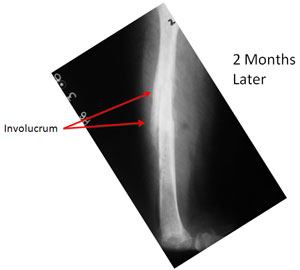

| The infection persisted and there is formation of new bone (Involucrum) around the dead necrotic bone (Sequestrum). |

At the time of presentation to us the Infected bone had weakened and broken (pathological fracture). The disuse osteoporosis of the bone is evident in the lower portion of the femur. The salt and pepper kind of appearance on the x-rays can represent a confusing picture of some kind of bone tumor. |

| The x-rays at 2 months after surgery show good progress of healing, resolution of the infection completely and improvement in the quality of the overall bone. The screws in the neck of the femur were applied because she developed a slipped capital femoral epiphysis (slippage of the growth plate of hip joint ball). |